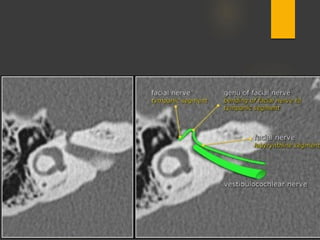

 Intratemporal facial nerv;

CN7 segments: lAC, labyrinthine, tympanic, mastoid segments

Geniculate ganglion = anterior genu

Posterior genu: Tympanic segment bends inferiorly to become mastoid

segment

Segments

 intracranial (cisternal) segment - zero branches

 meatal (canalicular) segment (internal auditory canal): 8 mm long, zero branches

 labyrinthine segment (IAC to geniculate ganglion): 3-4 mm long, 3 branches

(from geniculate ganglion)

 tympanic segment (from geniculate ganglion to pyramidal eminence): 8-11 mm

long, zero branches

 mastoid segment (from pyramidal eminence to stylomastoid foramen): 8-14 mm long, 3

branches

 extratemporal segment (from stylomastoid foramen to division into major branches): 15-

20 mm, 9 branches